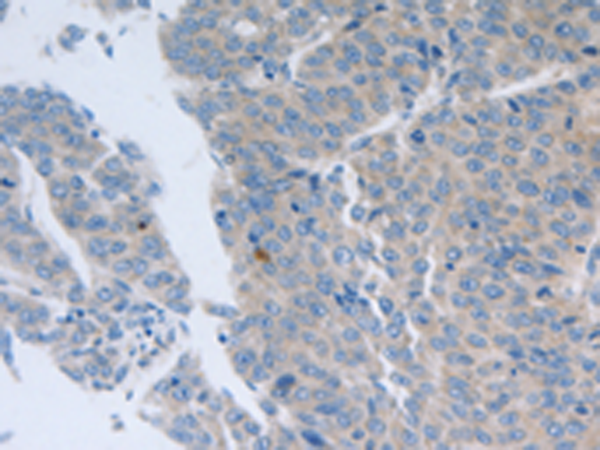

分类: 科研抗体货号: P11068别名: NR1, MRD8, GluN1, NMDA1, NMDAR1应用: IHC反应种属: Human, Mouse, Rat